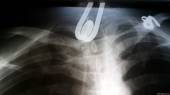

В Красноярске врачи извлекли из пищевода мужчины кипятильник. Об этом сообщает пресс-служба краевой больницы.

Молодого человека доставили в больницу 18 декабря. После осмотра было установлено, что в верхней трети его пищевода находится большой инородный предмет. В скором времени мужчина мог задохнуться.

После проведения рентгена было выявлено — в пищеводе застрял кипятильник. «С учетом того, что диаметр пищевода в спокойном состоянии 2–3 сантиметра, а кипятильник растянул его в 4–5 раз, операция по удалению инородного тела предстояла трудная», — рассказали в пресс-службе.

Сначала инородное тело пытались достать с помощью фиброгастроскопа (тонкой трубки для осмотра желудка), однако кипятильник был слишком большим и грубым предметом, поэтому таким способом его извлечь не удалось. Тогда врачи применили регидный эзофагоскоп — жесткую металлическую трубку со щипцами на конце. Сложность операции состояла в том, что при вводе эзофагоскопа есть большой риск разрыва пищевода.

Тем не менее врачи сумели за 20 минут извлечь из пищевода мужчины кипятильник. Спустя сутки он мог есть и был выписан из больницы. Врачам он отказался пояснять, как проглотил кипятильник, сказав, что сделал это «случайно».